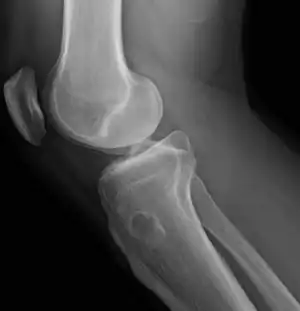

| Osteochondroma |